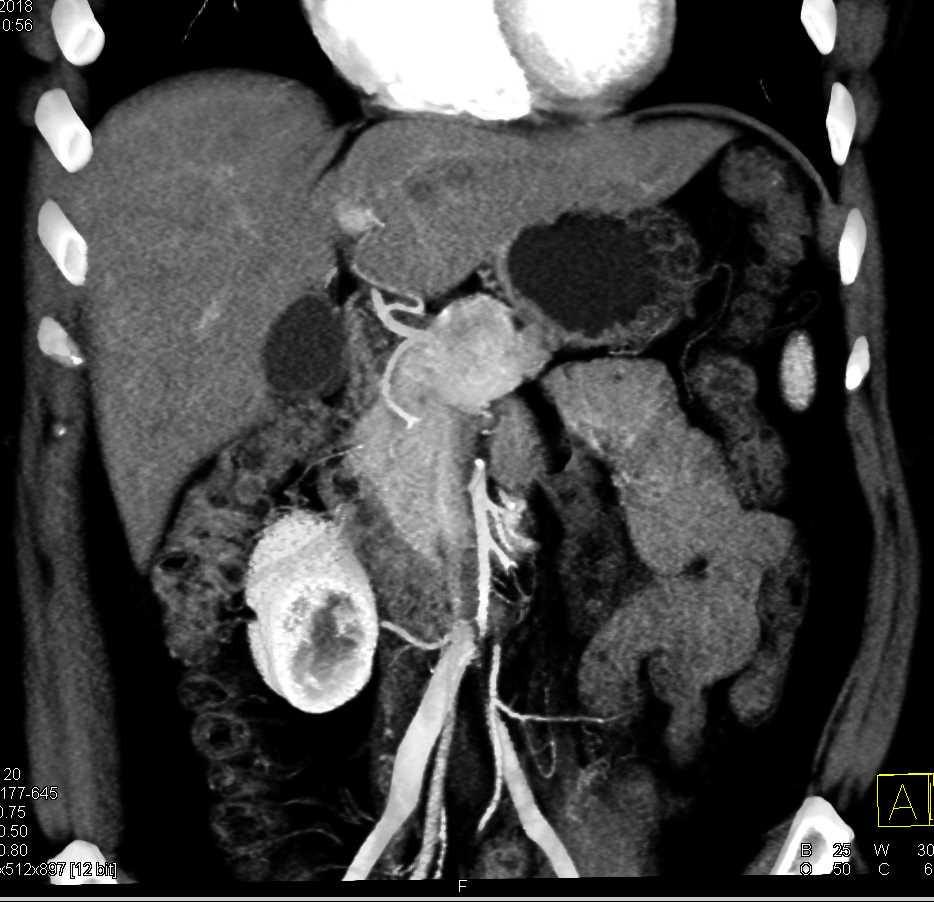

Neuroendocrine Tumor Body of Pancreas